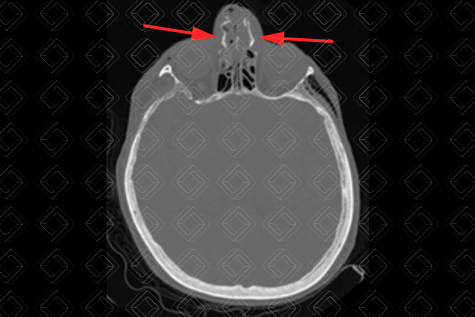

Texto alternativo para a imagem Créditos: Dra. Elazir Mota - Rio de Janeiro/RJ

Descrição das imagens: Tomografia computadorizada da face, cortes axial, coronal e reconstrução 3D. Múltiplas fraturas cominutivas e desalinhadas nos ossos nasais (setas vermelhas na primeira imagem) e septo nasal (seta vermelha na segunda imagem). Observa-se ainda o enfisema de partes moles decorrente do trauma (estrela).